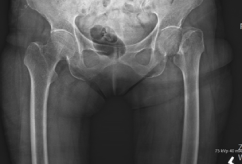

Case 1: 70-year-old female with bilateral hip osteoarthritis

Romosozumab ➝ Denosumab